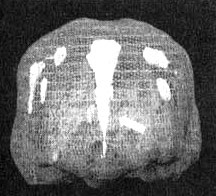

Поясная извилина

Трехмерное изображение — активный мозг, вид спереди

Глубоко в центральной части мозга, вдоль лобных долей, проходит поясная извилина. Это та часть мозга, которая позволяет вам переключать внимание с одного объекта на другой, переключаться с одной мысли на другую, видеть различные варианты решений.

Считается, что она отвечает и за ощущение безопасности.

На мой взгляд, точнее всего функции этой области мозга можно выразить термином «когнитивная гибкость».